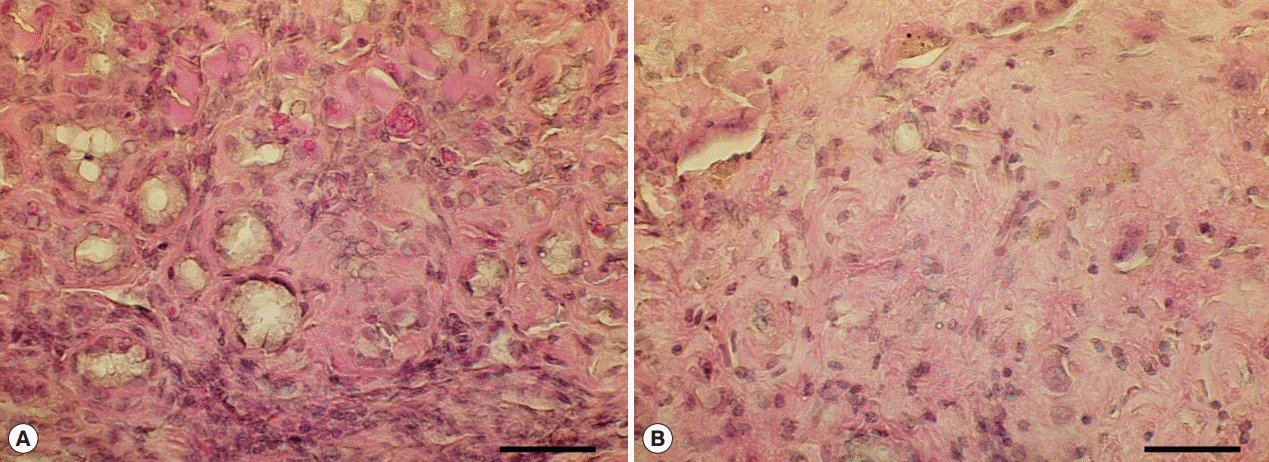

Histopathological examination revealed bile duct dilatation and proliferation of ductal epithelial cells in all C. sinensis infected groups (Cs, Cs+DC, Cs+NDMA, and Cs+NDMA+DC). Cs (b) group showed typical hyper-proliferative bile ducts due to C. sinensis infection. In Cs+NDMA+DC group, fibrotic zones were observed (Fig. 3B-h) and higher magnifications demonstrated hyperplastic changes and extensive fibrosis in these areas (Fig. 5; Supplementary Fig. S4), however, no CCA developed. The large mass forming lesions observed in Cs group confirmed as glycogen rich clear cell hepatocellular adenoma surrounded by eosin stained healthy hepatocytes. The mass contained clear cell hepatocytes rich in glycogen as revealed by PAS/DPAS staining (Fig. 6). The other mass forming lesions observed in Cs+DC group diagnosed as peliosis resulting from dilated sinusoid (Fig. 6). The center of this cystic lesion marked with coagulative necrosis without any inflammatory cells (Fig. 3B-f; indicated with asterisk). Blood filled cavities also evident from histopathology (Fig. 3B-f; arrow).

The present study observed MFLs and nodules particularly in the Cs group or in the Cs with one or both carcinogenic chemicals (NDMA, DC) groups. The mass lesions suggested a certain role of C. sinensis worms to produce the pathology. Though hepatocellular adenoma is a pathological event in DC treated mice [21], we observed it in a mouse of Cs group. The hepatocellular adenoma is a rare unexpected finding for C. sinensis infection. Among various types, it falls under the category of glycogen storage disease (glycogen rich clear cell hepatocellular adenoma). Moreover, the Cs+DC group showed peliosis which was also a noble instance for both C. sinensis and DC treatment. In the formation of peliosis, sinusoidal dilation created extensive pressure on surrounding blood vessel causing such ischemic damage. No CCA was evident from the Cs+ NDMA+DC group; however, it showed highest mean intensity and highest average volume of nodules. Other histopathological findings such as bile duct dilatation, hyperplasia was common in all C. sinensis infected groups but progressed to extensive fibrosis in Cs+NDMA+DC group. The histopathological findings suggest that the worms made the histological changes although most of the mice did not have the worms in their liver. Most of the inoculated worms invaded into the intrahepatic bile duct but could not survive and discharged within a few weeks after infection [6]. On the other hand, chemical treated groups (NDMA or DC alone) did not show any detectable changes revealed by histopathology.